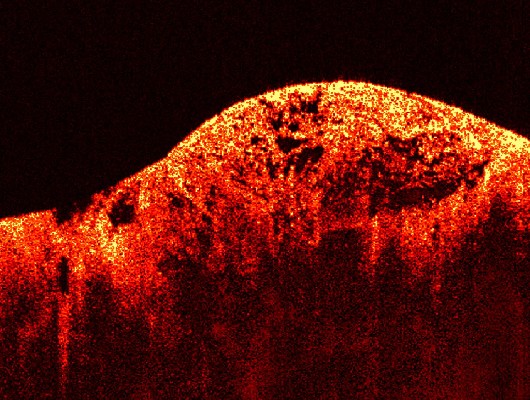

En definitiva, son un tipo de cáncer que se origina en los tejidos blandos (músculos, grasa, vasos sanguíneos, nervios, tendones, ligamentos y otros tejidos conectivos) o en los huesos. A diferencia de los carcinomas (que se originan en células que recubren órganos o glándulas, como la piel o el revestimiento intestinal), los sarcomas son de origen mesenquimal.